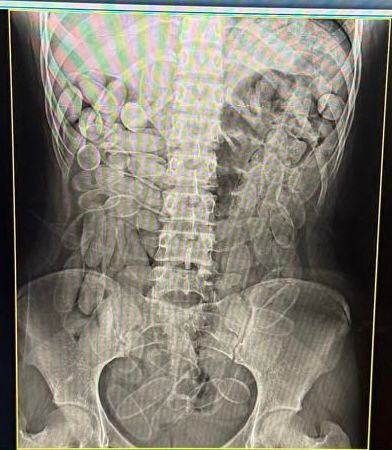

Diante da situação, ambas foram encaminhadas à Santa Casa de Corumbá, onde um exame de raio-x constatou que havia várias cápsulas do entorpecente no organismo. Elas confessaram terem engolido, cada uma, 102 cápsulas, para fazer o trabalho de "mula".

No dia 14 de janeiro, bolivianas foram presos com 102 cápsulas de cocaína no estômago (Foto: Divulgação / Receita Federal)